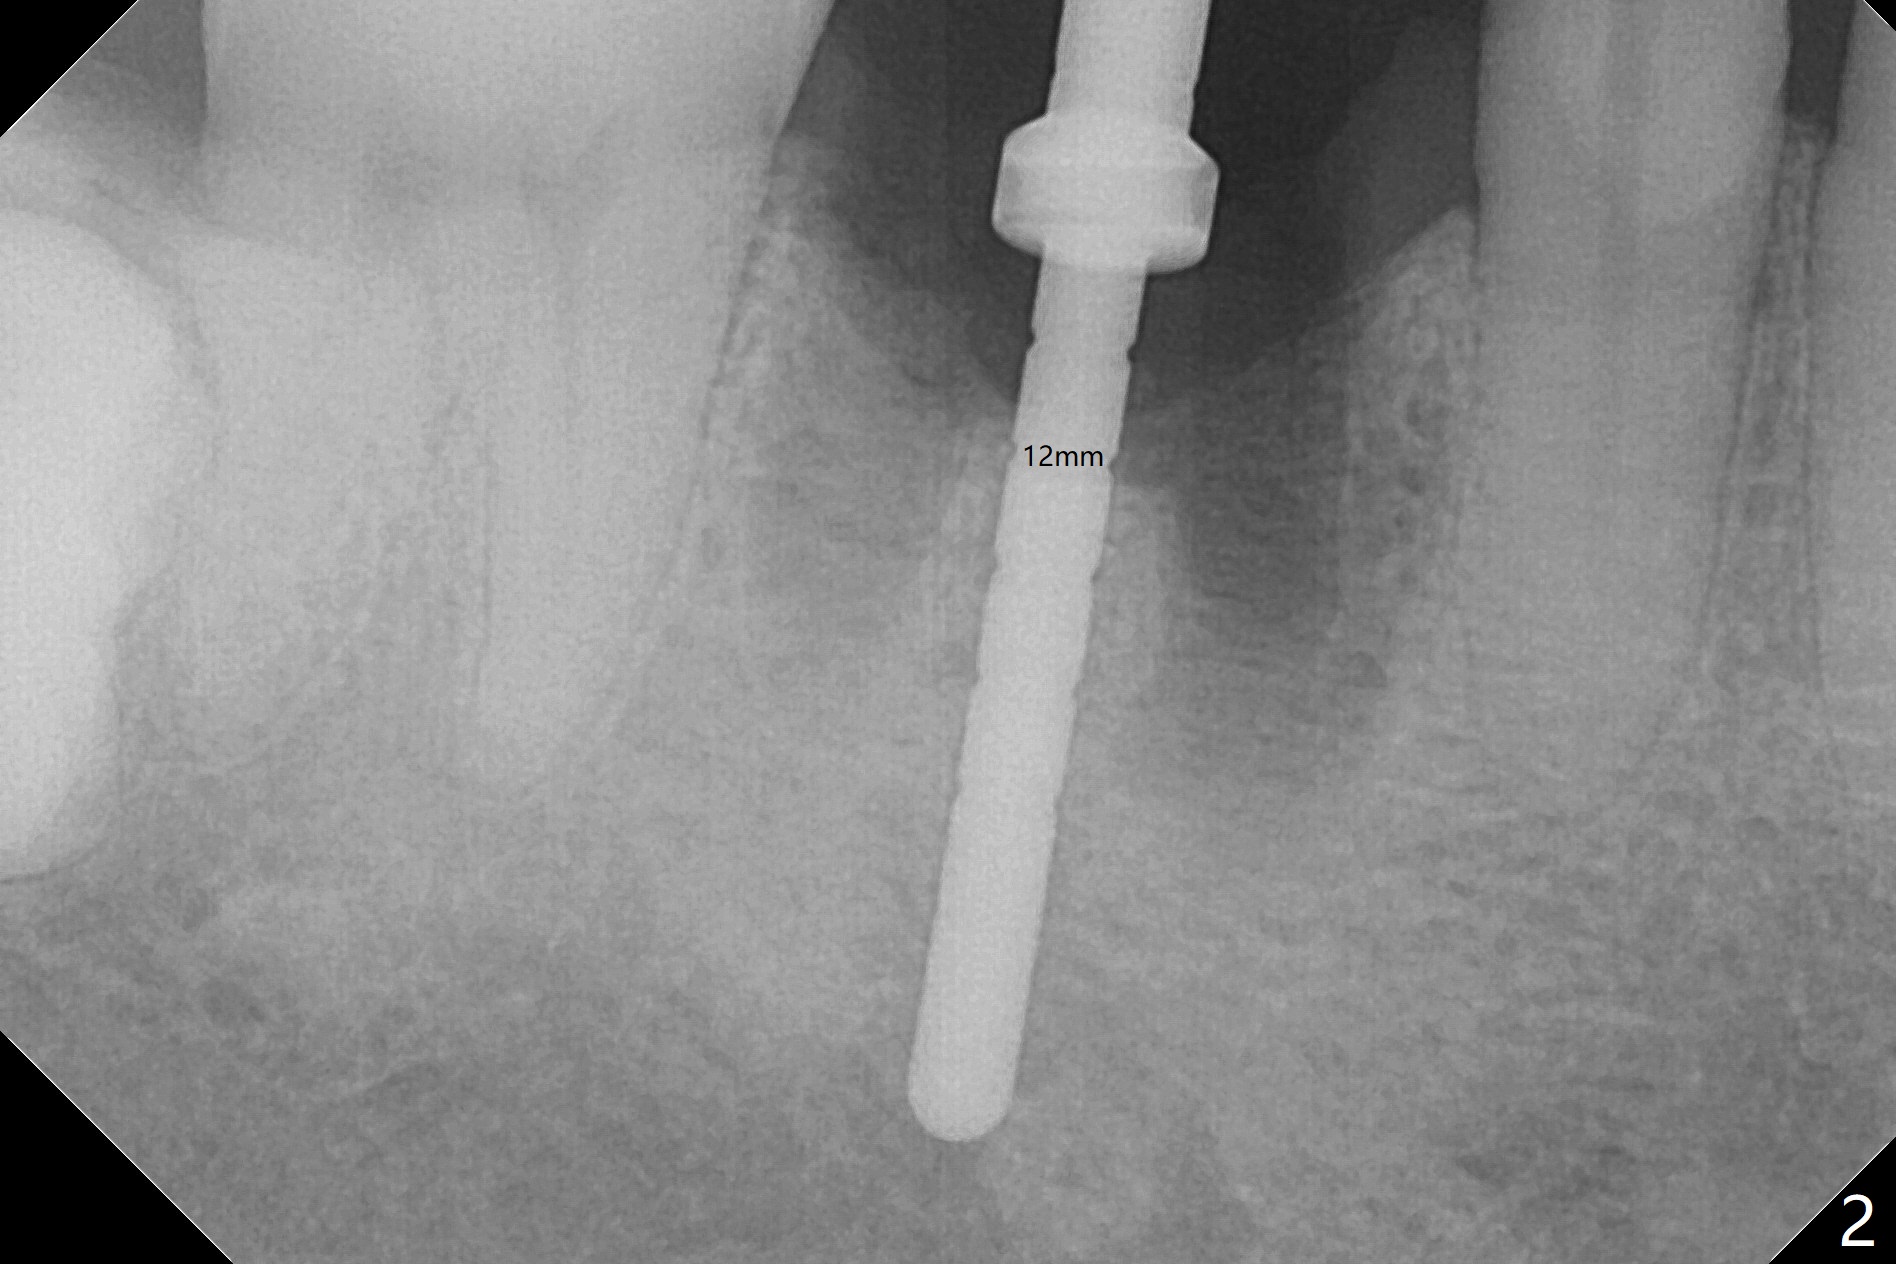

After extraction of the tooth #30, the mesiobuccal plate is found to be lost, corresponding to the fistula (Fig.1 <). Osteotomy is initiated in the flattened septum (lingual) for 13 mm (Fig.2). The patient feels pain when larger drills are being used. Marcaine has to be injected in an infiltration manner for pain control. When a 4.5x10 mm dummy implant is inserted with 55 Ncm, the end of the osteotomy (Fig.3 white line) is close to the Inferior Alveolar Canal (red dashed line). When a definitive implant (Fig.4: 4.5x11.5 mm) is placed with primary stability, there is an apical space (Fig.5 white double arrows). There is moderate postop pain. A shorter implant (10 mm) should be tried when the bone is dense. It will be associated with less pain. The fistula disappears 7 days postop (Fig.6). Although the patient appreciates that the pain is gone, there is atrophy mesiobuccally 2 months postop (Fig.7 *). The implant seems to be have been placed too buccally (Fig.8). With loss of the buccal plate, the implant should be placed away from it to prevent periimplantitis. The abutment is changed from 6.5x4(4) to 6.5x5.5 (3) mm with fabrication of a new provisional. The buccal margin is still supragingival 6 months postop and prep lower before impression. The mesial and distal sockets appear to have healed (Fig.9). When the crown is cemented, the mesiobuccal papilla is present (Fig.10 *), while the mesiolingual one is apparently absent (Fig.11 *). Using a temporary abutment and relining the provisional multiple times would increase the chance of rebuilding the missing papilla. The bone density around the implant increases 11 months post cementation (Fig.12). The dense (apparently cortical) bone seem to grow over the implant plateau 11 months post cementation (Fig.13 <).